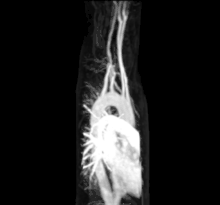

![]() The human circulatory system (simplified). Red indicates oxygenated blood carried in arteries. Blue indicates deoxygenated blood carried in veins. Capillaries, which join the arteries and veins, and the lymphatic vessels are not shown. | |

Other more invasive means can also be used. A cannula or catheter inserted into an artery may be used to measure pulse pressure or pulmonary wedge pressures. Angiography, which involves injecting a dye into an artery to visualise an arterial tree, can be used in the heart (coronary angiography) or brain. At the same time as the arteries are visualised, blockages or narrowings may be fixed through the insertion of stents, and active bleeds may be managed by the insertion of coils. An MRI may be used to image arteries, called an MRI angiogram. For evaluation of the blood supply to the lungs a CT pulmonary angiogram may be used.